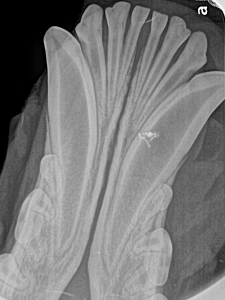

Feline Full Mouth Radiograph example